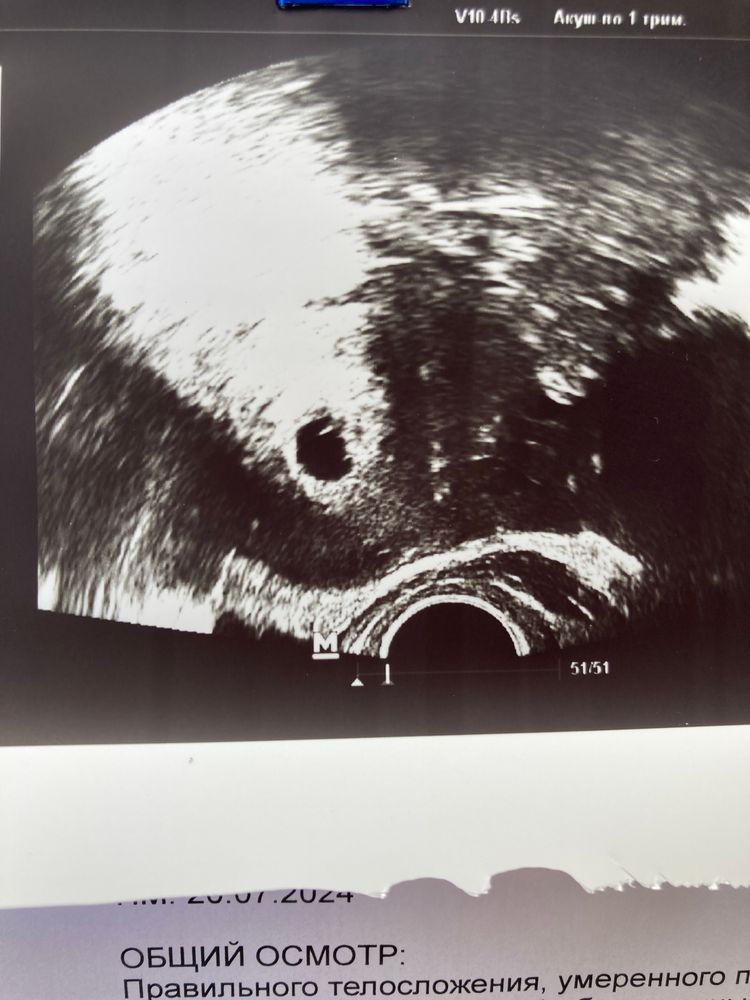

Два эмбриона по узи Первый скрининг пройден 🥰🤞🏼